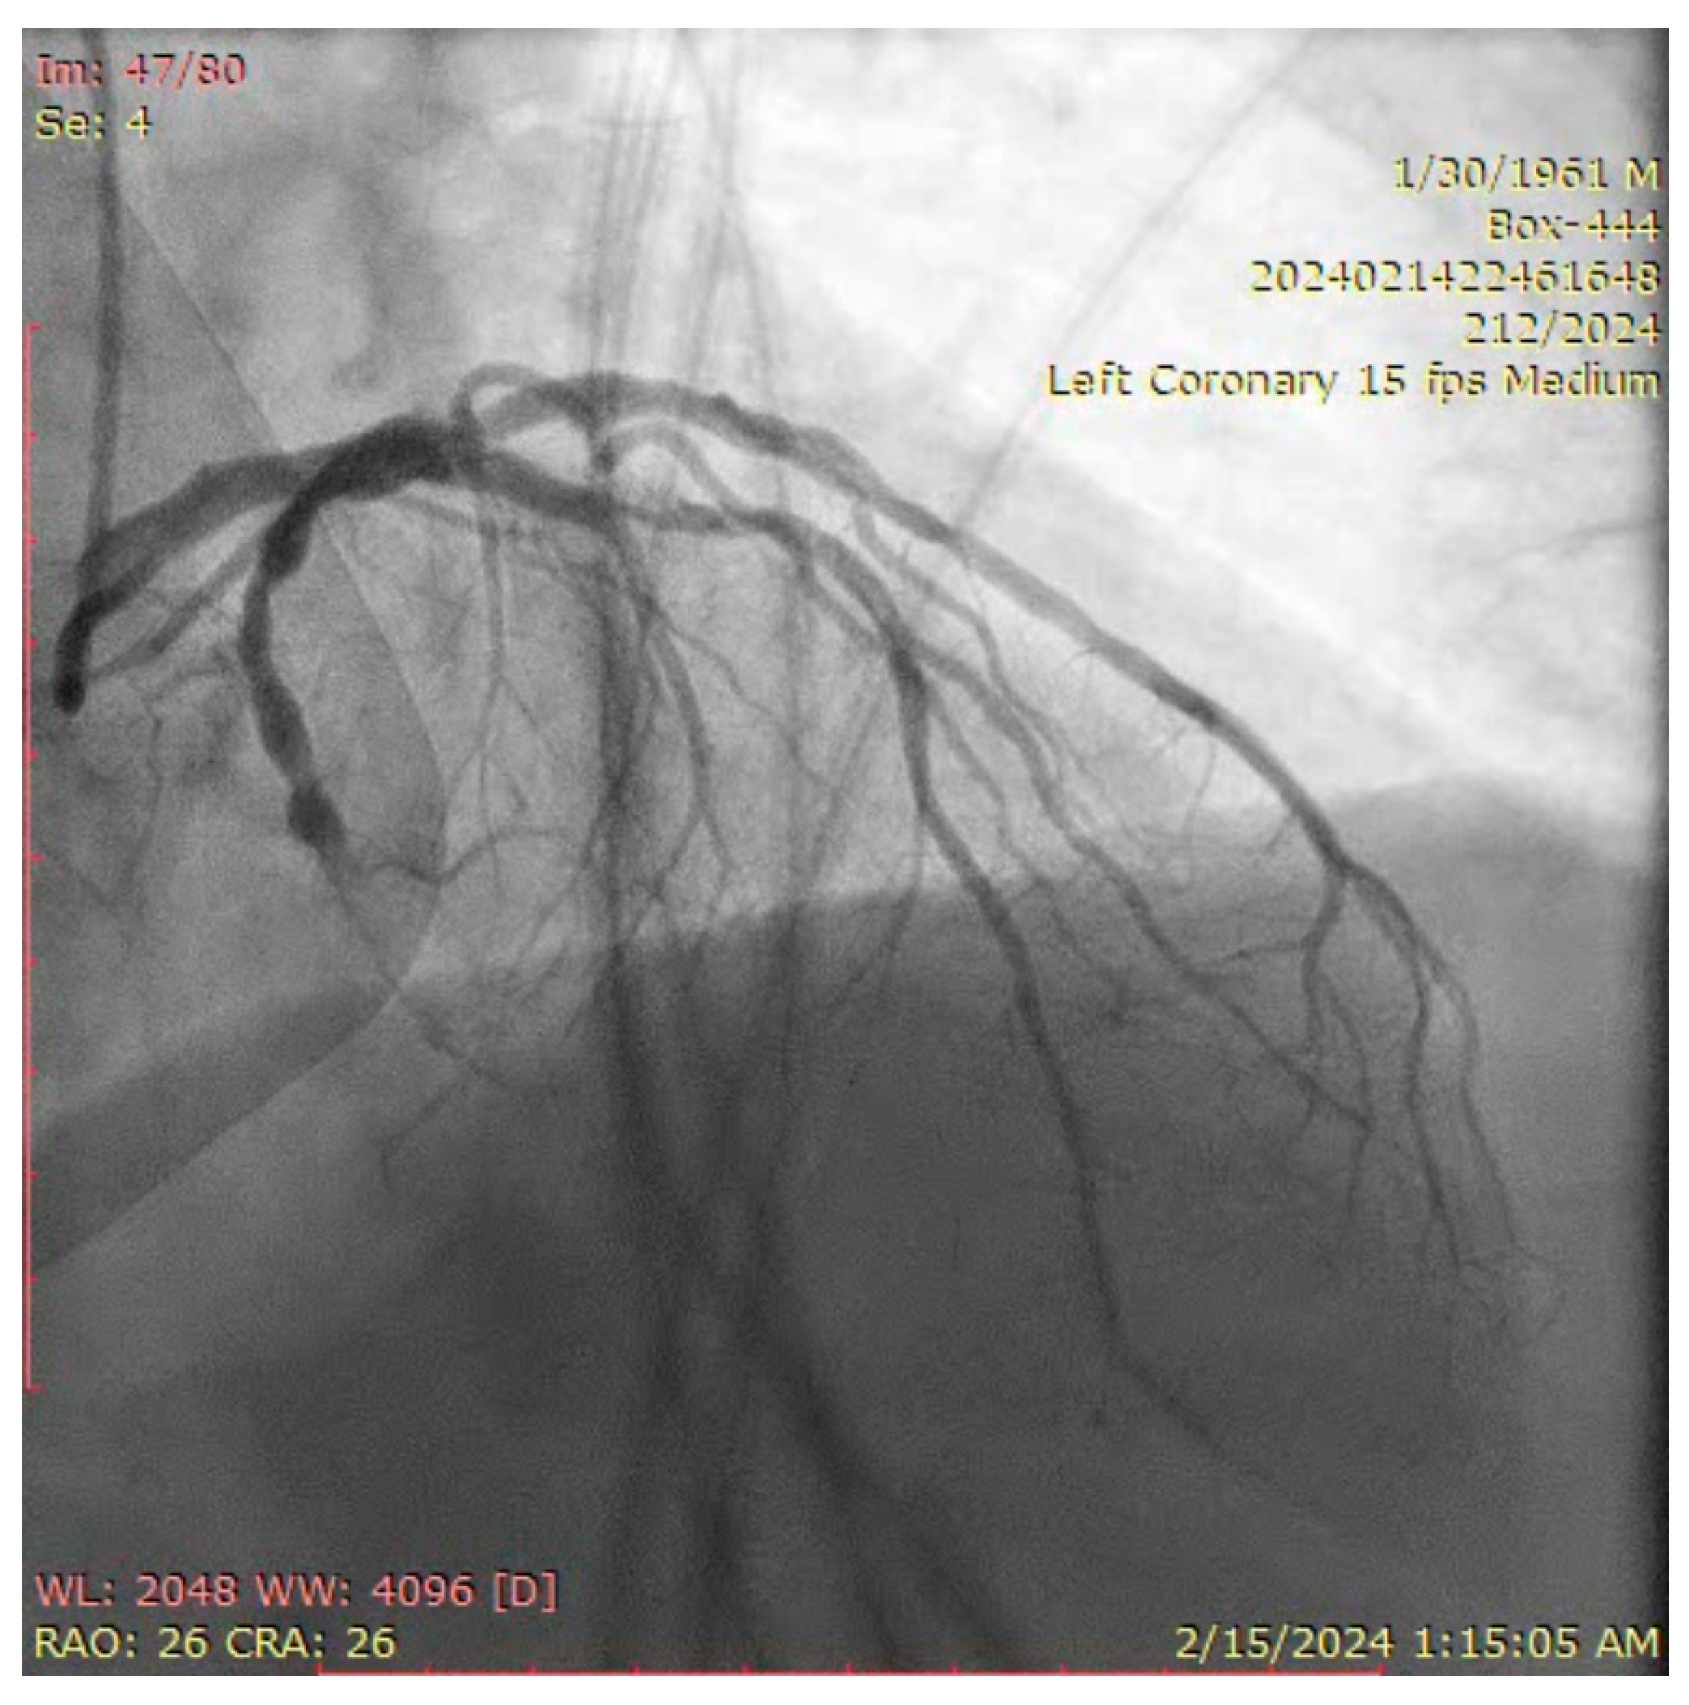

The ostium of left anterior descending artery (LAD) presented a 75% stenotic lesion, with the proximal segment displaying a 90% lesion (Figure 3). The left circumflex artery (LCX) revealed a 75% stenotic lesion of the ostium and tapered disease of its distal segment with areas of ectasic disease, with the ostium of the ramus intermedius (RI/RM) showing a 75% lesion (modified Medina classification 0-1-1-1 [4]) (Figure 4, Figure 5, Figure 6, Figure 7, Figure 8, Figure 9 and Figure 10).

Figure 3.

Left coronary artery (Right anterior oblique caudal (RAO) caudal view).